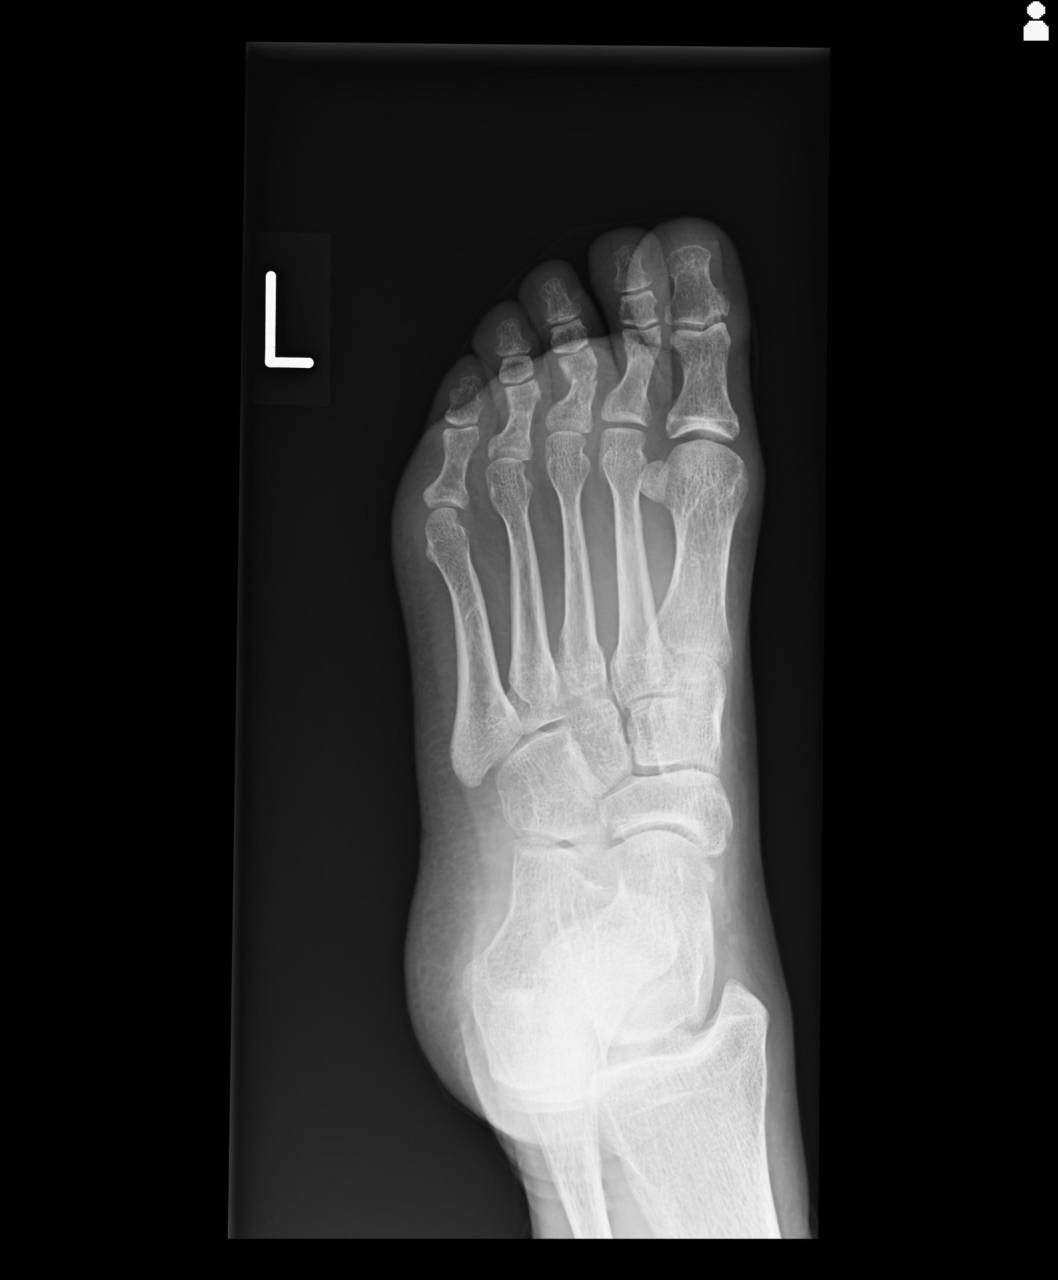

当整骨院が提携している病院にてレントゲン検査を依頼し、撮影した画像を確認すると左第3趾基節骨骨頭骨折が確認できました。

レントゲン画像上も変形していることが分かったため、整復操作を行いキャスト(ギプス)等で転位しないように固定を行い、固定下で微弱電流にて骨の組織修復を行いました。